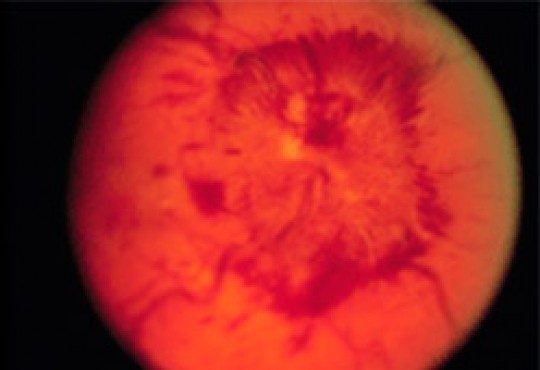

El nervio óptico se ve como un órgano redondeado, plano, de bordes netos. Cuando hay edema de papila los bordes se ven borrosos y sobreelevados. Se suelen ver hemorragias y en ocasiones exudados, que son puntos blancos (ver figura).

Img Edema Papilar